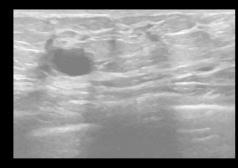

applyingMeanFilter,theresultisshowninFigure2(d).The outcome of the Median Filter is shown in Fig 2(e). Figure 2(f) depicts the outcome of using the Bilateral filter, while Figure 2(g) depicts the result of using the Anisotropic Diffusion filter, Figure 2(h) portraits the result of Total Variation filter and Figure 2(i) shows the result of NLM filter.

TheoriginalBUSimageisdisplayedinFigure2(a). The output of a Wiener Filter without FFT is shown in Figure2(b),whichusesa3x3kernel.Theresultofapplying the Wiener filter with FFT is shown in Figure 2(c). After

(a) (b) (c) (d) (e) (f) (g) (h) (i) Fig2.(a)Original BUSimage (d)MeanFilter (g)Anisotropic DiffusionFilter (b)WienerFilter withoutFFT (e)MedianFilter (h)TVFilter (c)WienerFilter withFFT (f)BilateralFilter (i)NLMFilter